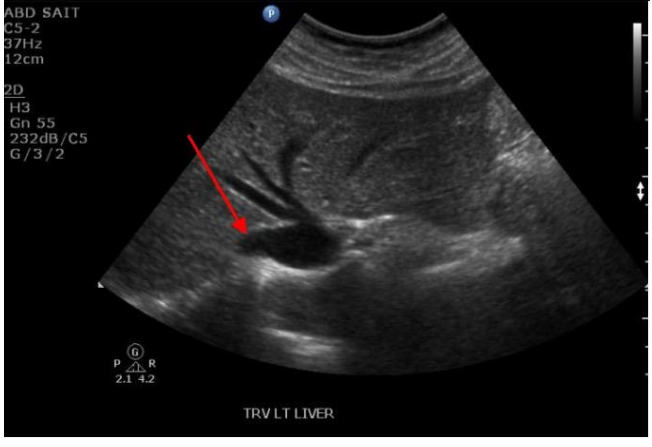

Q

Label the red and yellow arrows

A

Red arrow: Left Hepatic vein

Yellow arrow: Pancreas neck